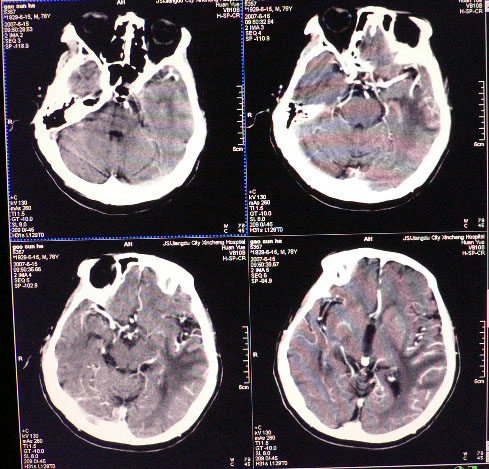

标题: CT8712:男性,78岁,失语,意识障碍,脑转移瘤 [打印本页]

男性,78岁,失语,意识障碍1天

平扫ct值为40-45hu,增强为不均匀强化,ct值为81-85hu

皮层下厚壁花环状高密度影,明火显强化,大范围指样水肿,支持转移瘤诊断。其后上方好像还有小灶。

发生于质下,软组织影,形态不规则,周边大片水肿,明显环状强化,中间低密度液化坏死,建议结合临床

从发病部位,病灶强化特点、周围水肿情况支持脑转移瘤诊断,可进一步检查查找原发灶。